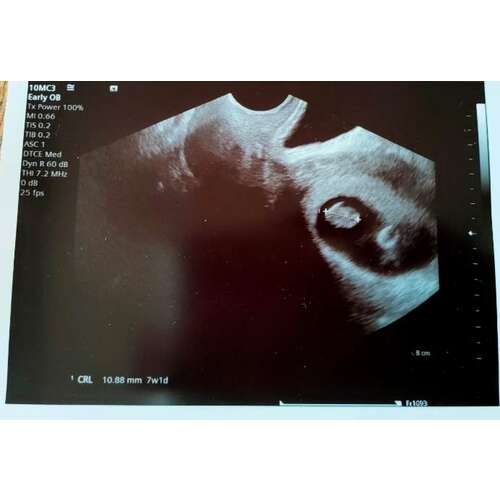

I added a photo of my ultrasound from a year ago when I was 7 weeks pregnant. You can see the dark oval with two dots on the right, the top dot is my son, the lower dot is the yolk sac.

This is not a pregnancy. It is very normal that there are soms darker spots in your uterus, also if you are not pregnant. This is just the typical ultrasound image. If you are pregnant, you can clearly see black ‘holes’ filled with amniotic fluid. And in the sac, you would also be able to distinguish clear forming embryos. This is my ultrasound with 7 weeks 6 days. You are not pregnant in your ultrasound. However, if you are pregnant less than 6 weeks it is sometimes normal to not be able to see anything. How far along would you be according to your last menstrual cycle?